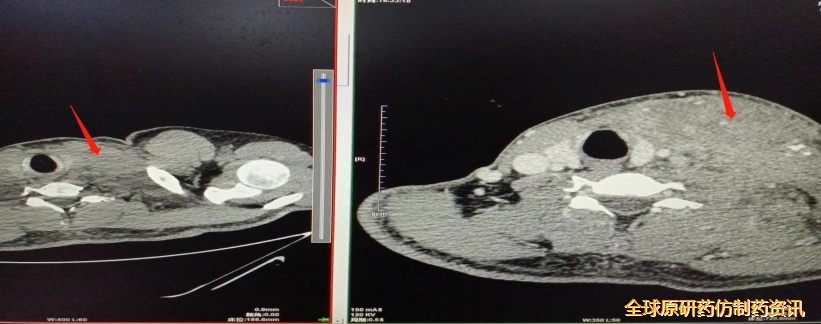

胸腹盆CT平扫(2022.03.29):左锁骨上窝、腹膜后、盆腔多发肿大淋巴结

图1. 2022.03.29检查结果